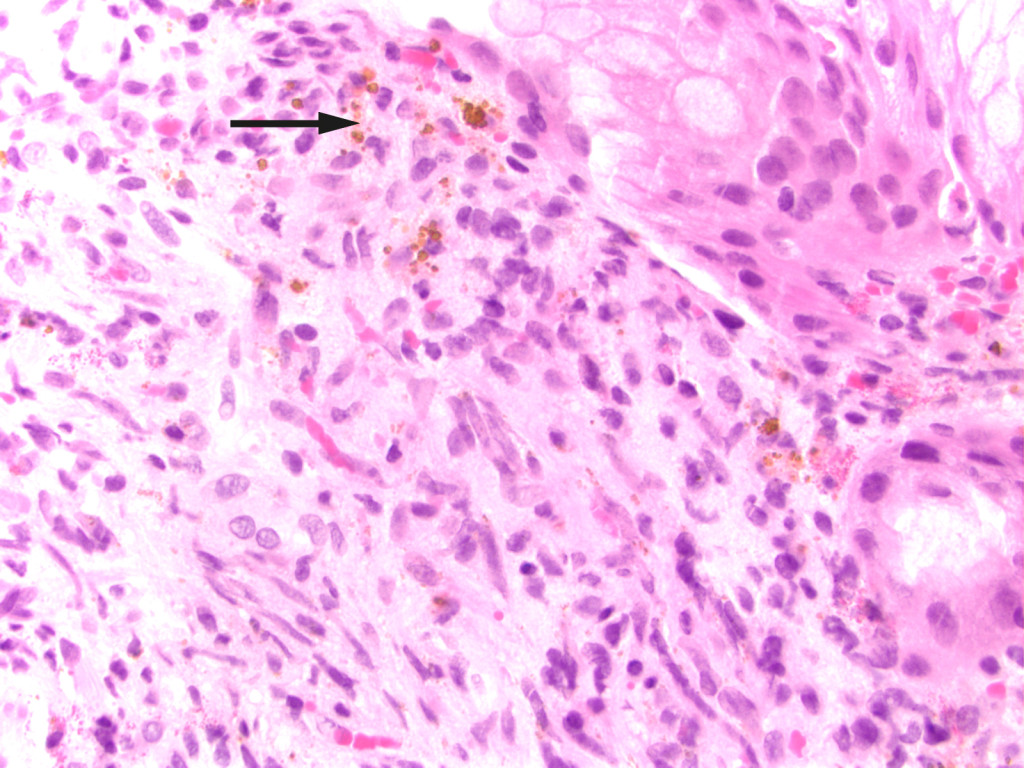

After this episode, he never fully recovered. He was hospitalised yet again and underwent another gastroscopy, which revealed three reddish, pillow-shaped, haemangioma-like lesions in the stomach. The lesions were biopsied. When the macroscopic gastroscopy findings were compared with an endoscopy atlas, they were found to be pathognomonic for a gastrointestinal manifestation of Kaposi's sarcoma (2). The pathologist was asked to examine the gastric tissue biopsies in light of this possibility. The patient also pointed out purplish skin lesions on his right forearm and left wrist that had increased in size over the last five months (Figure 1). The skin lesions on the arm were biopsied, and histological testing confirmed Kaposi's sarcoma in these biopsies as well as those from the stomach (Figure 2). Both biopsies showed HHV8 (human herpesvirus 8)-positivity. The lymph node biopsy from five years earlier was re-evaluated and deemed also to be consistent with Kaposi's sarcoma (Figure 3). Following the diagnosis, treatment was started with intravenous liposomal doxorubicin. Despite treatment, the disease progressed and spread to the liver, and the patient died just over two years after the diagnosis was made.

Figure 3 Lymph node with capillary proliferation. Spindle cells and extravasated erythrocytes in the capsule (arrow). Normal…

Figure 3 Lymph node with capillary proliferation. Spindle cells and extravasated erythrocytes in the capsule (arrow). Normal lymphoid follicle can be seen lower right. HE stained (haematoxylin-eosin).

Histopathological findings are identical in the four types, with the most typical histopathological finding being spindle cells. The disease progresses in three histological stages: the first is the 'patch stage' and is characterised by flat, macular lesions. The next stage is characterised by plaques, while the final, tumour stage, is characterised by nodular lesions. These histological changes can easily be overlooked (5).